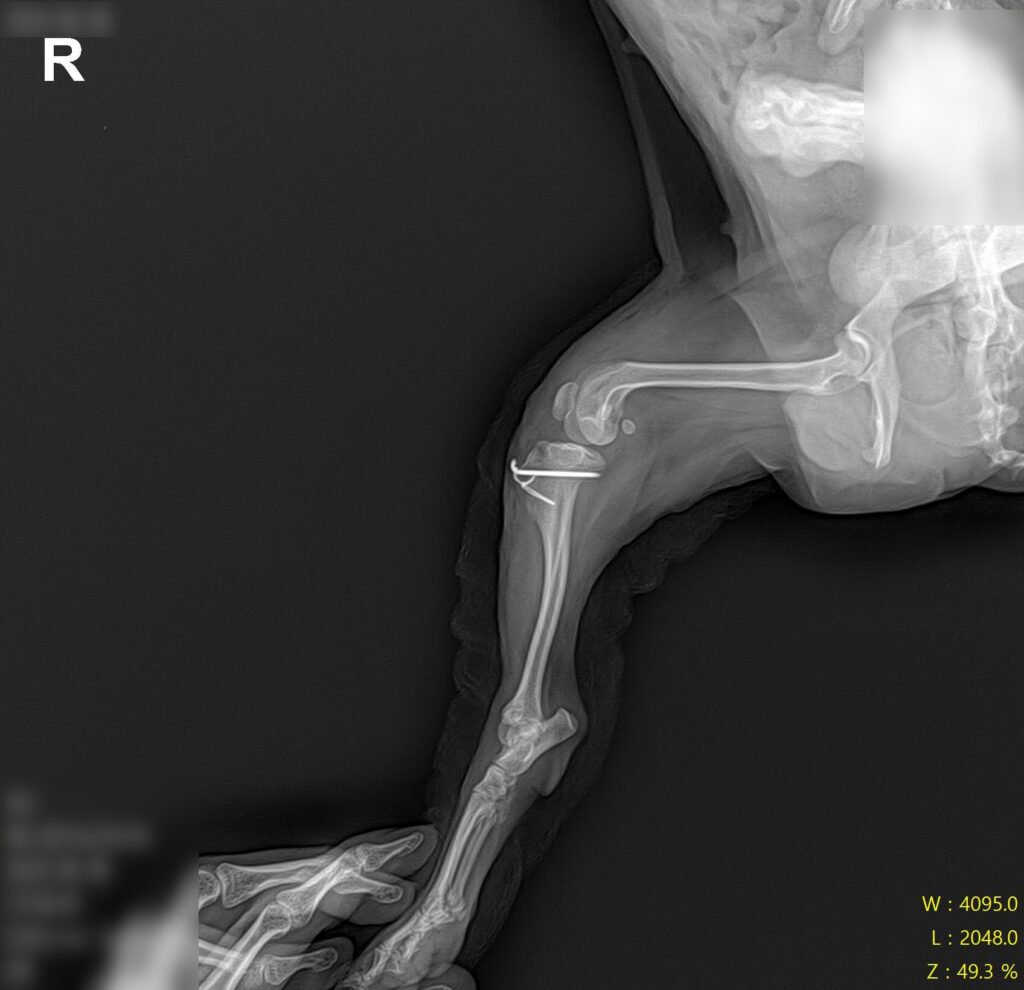

마취 전 방사선 검사 / 출처: 라온동물메디컬센터

정형학적 검사와 방사선 영상 검사를 진행한 결과, 슬개골탈구 4기(말기, terminal) 소견이 확인되었습니다. 슬개골이 완전히 고정 탈구된 상태였고, 활차구의 심각한 평탄화와 경골 조면의 내측 편위, 다리뼈의 비틀림이 동반되어 있었습니다.

2년 전 3기 진단 당시와 비교하면 그 사이 조용히, 그러나 빠르게 진행된 것이었어요. 보행이 크게 불편해 보이지 않았던 이유는 강아지가 변형된 뼈 구조에 스스로 적응하며 걷고 있었기 때문입니다.